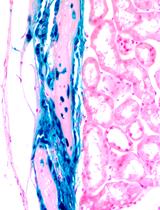

Liver fibrosis results from the excessive collagen deposition (collagen scar) by activated hepatic stellate cells (HpSCs), leading to the inhibition of normal liver regeneration and function. Fibrogenesis is a complex mechanism involving both the synthesis and degradation of matrix proteins by different cell types, mainly macrophages in the liver. Carbon tetrachloride-induced fibrosis (CCl4) and cirrhosis is one of the oldest, simplest and probably the most widely used toxin-based experimental model for the induction of fibrosis. Here we have explained experimental animal model of liver fibrosis using CCl4, injecting twice a week for a period of 8 weeks. In these fibrotic mice, bone marrow (BM) derived CD45+ cells were transplanted via intrasplenic route after 8 weeks of CCl4 injection, and half of the CCl4 dose was continued till the end of the experiment to know the effect of transplanted cells on liver fibrosis and regeneration. So far, crude bone marrow (BM) cells or mesenchymal stem cells (MSCs) have been used for the treatment of liver fibrosis. Low survival rate, less fibrolytic and profibrogenic properties of MSCs remain the major concerns for inadequate recovery of liver from fibrosis. This led us to investigate BM cells devoid of mesenchymal lineage that is CD45+ cells for the antifibrotic effect as this population consisting of mononuclear cells which are the precursor of macrophages and may involve in the scar degradation process. Cells transplantation can be followed in different ways like intrasplenic infusion, tail vein injection and ectopic cell transplantation in experimental animal models. The survival of the cells after ectopic transplantation is less when compared to tail vein and intrasplenic infusion. Intrasplenic route of transplantation is effective in engraftment and long term survival of the donor cells especially in case of liver disease models. This protocol describes fibrosis mouse model development, intrasplenic route of cell transplantation and tracking of the donor cells after transplantation.